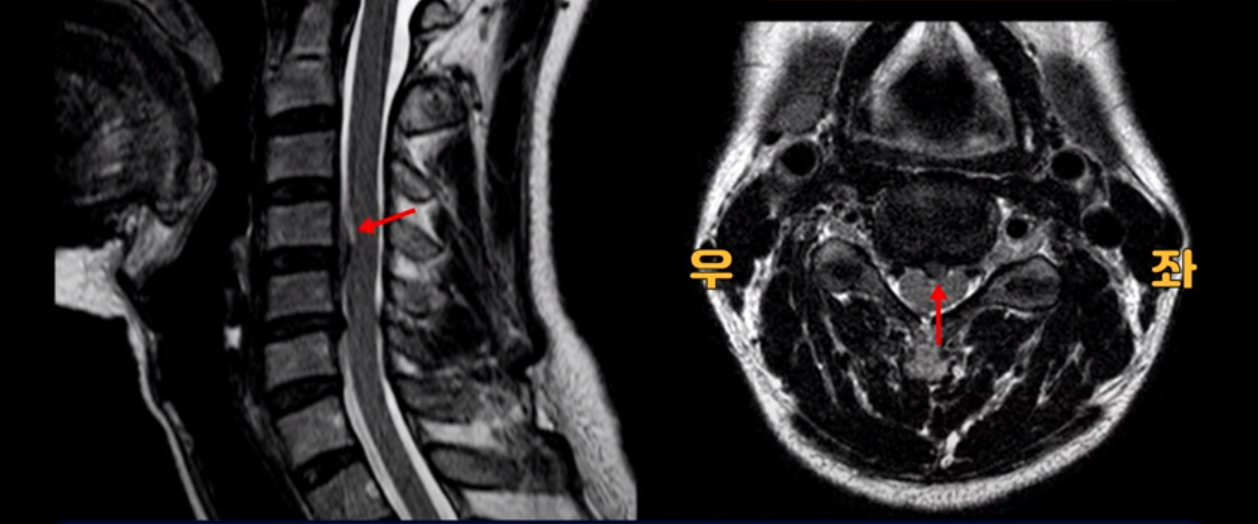

우선 이분 MRI를 보기 전에 이분 증상에 대해 말씀 드리면 오른쪽 팔저림과 방사통 및 어깨 통증이 있습니다. MRI를 보면 4번 5번에 디스크 파열이 보입니다.

밀려나온 디스크가 위로 타고 올라가 있는데 보시다시피 가운데로 밀려 나와 있습니다.

그래서 이게 오른쪽 통증의 원인일 수도 있고 아닐 수도 있습니다. 5번 6번은 왼쪽으로 밀려 나와있으니까 오른쪽 통증의 원인이 아닙니다.

이런 게 협착을 일으킵니다. 그래서 우선 오른쪽 신경구멍 즉 추간공을 살펴보면 맨 위의 한마디를 빼고는 다 좁아져 있습니다.

특히 5번 6번 구멍이 가장 좁습니다. 이걸 협착이라고 합니다.